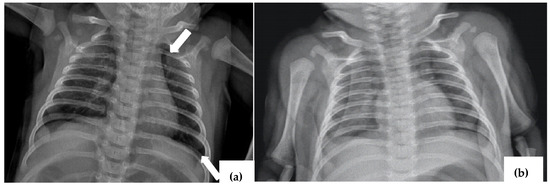

2.3. Case 3